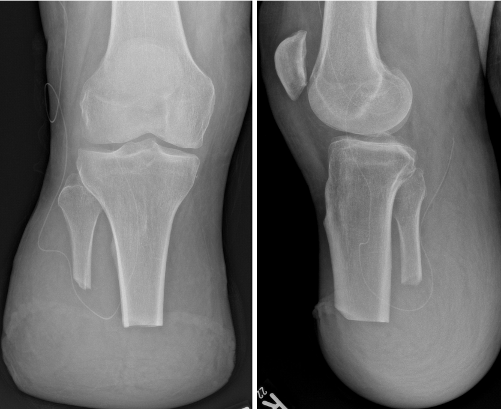

Abbildung 2 [Abb. 2]

Abbildung 2: Burgess-Amputation